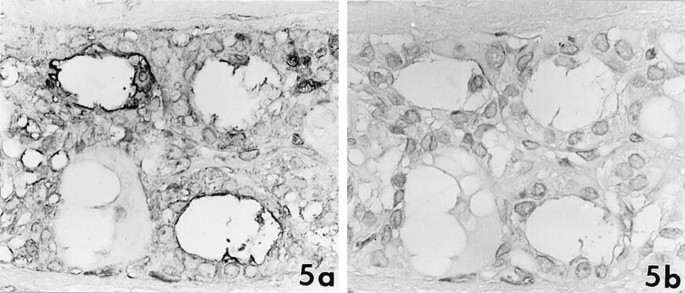

In 43 papillary carcinomas, DU-PAN-2 and CA19–9 were expressed in 42 cases (98%) and 36 cases (84%), respectively. Lea and Leb were occasionally or focally present in 14 (33%) and 21 (49%) cases. The number of tumor cells that expressed DU-PAN-2 was necessarily greater than that expressing CA19–9 and Lea or Leb. The majority of DU-PAN-2–positive cases showed moderate (2+) or marked (3+) staining. Six cases were positive for DU-PAN-2 but negative for CA19–9, Lea, and Leb (Fig. 3). These antigens showed a tendency toward pronounced expressions in invasive elements of tumors in the presence or absence of fibrous stroma (Fig. 4). All of eight follicular variants were positive for DU-PAN-2 but restrictedly stained for CA19–9, Lea, and Leb (Fig. 5). These reaction products were distributed predominantly on the apical membrane of the tumor cells but also occasionally around the cell membrane or the cytoplasm. Colloid substances were rarely stained for these antibodies, and no stromal components expressed the antigens.